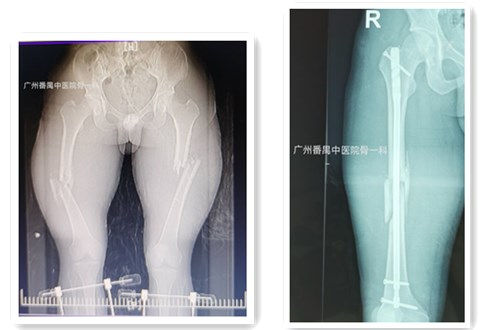

图1:术前 图2:术后

近日,我院骨伤一科(创伤骨科)成功为一例因车祸引起的双侧股骨干粉碎性骨折患者施行了带锁髓内钉微创接骨术,患者术后第二天即可以早期下地进行功能锻炼。患者及其家属对微创接骨术的效果非常满意。

完善相关检查后,科主任毛勇立即组织创伤骨科团队针对该患者的病情特点进行术前讨论,制定了精心的治疗方案,并为患者施行了精准的带锁髓内钉微创接骨术。患者术后次日即恢复关节屈伸活动功能,并可扶拐早期下地功能锻炼。